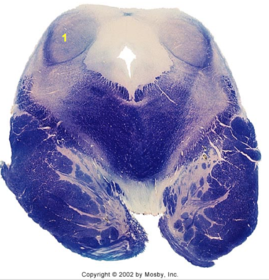

| Head of caudate | |

| Anterior commissure | |

| Thalamus | |

| Substantia nigra | |

| Optic tract | |

| Dentate nucleus | |

| Pons | |

| Longitudinal pontine fibers | |

| Uncus | |

| Superior cerebellar peduncle | |

| Red nucleus | |

| Corticospinal tract (dark) | |

| Pontine nuclei (pale) | |

| Transverse pontine fibers (dark) | |

| Inferior olive | |

| CTT | |

| Medial lemniscus | |

| Nucleus cuneatus | |

| Superior colliculus | |

| Inferior colliculus | |

| Optic nerve | |

| Cerebellum | |

| 4th ventricle | |